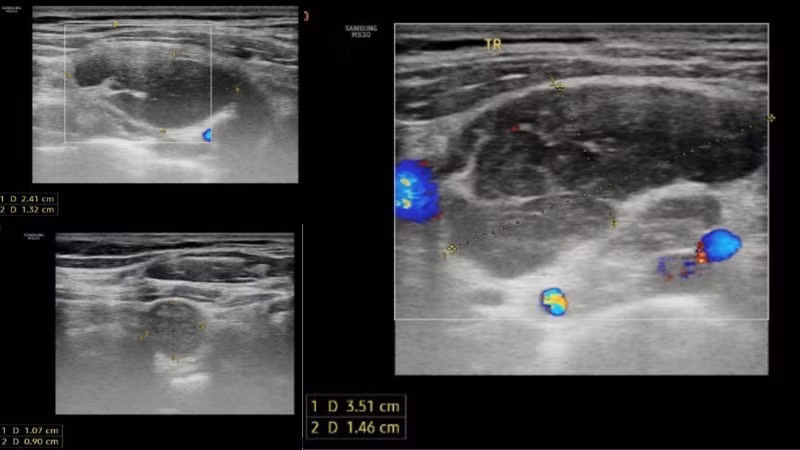

Kết quả siêu âm tuyến giáp ghi nhận hạch vùng cổ và hố thượng đòn hai bên.

Siêu âm tuyến giáp ghi nhận hố thượng phải có vài hạch giảm âm, bờ và ranh giới rõ, còn cấu trúc rốn hạch, hạch lớn kích thước 24x13mm. Hố thượng đòn trái có vài hạch giảm âm, bờ và ranh giới rõ, không rõ cấu trúc rốn hạch, hạch lớn kích thước 35x15mm.